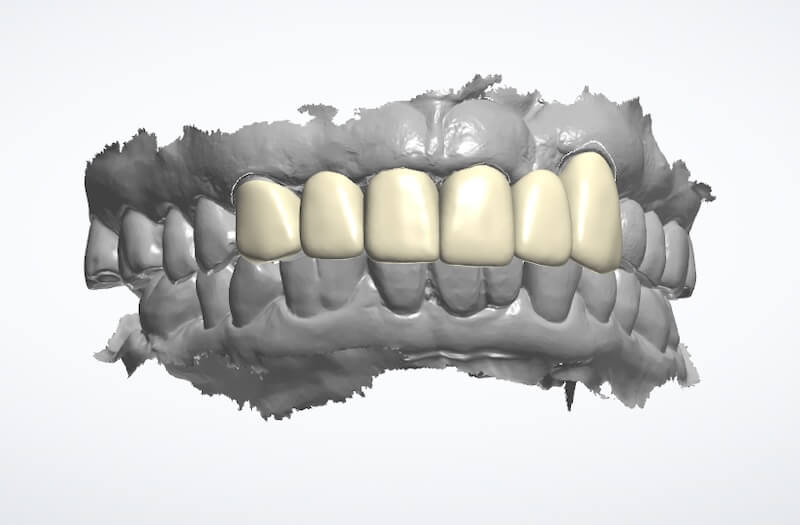

在這個相對健康的牙周環境狀態下,我們利用DSD數位微笑設計,全數位化的口內掃描並製作出第二組臨時假牙,透過這組假牙置放在口內和她討論未來正式假牙的外型與顏色。